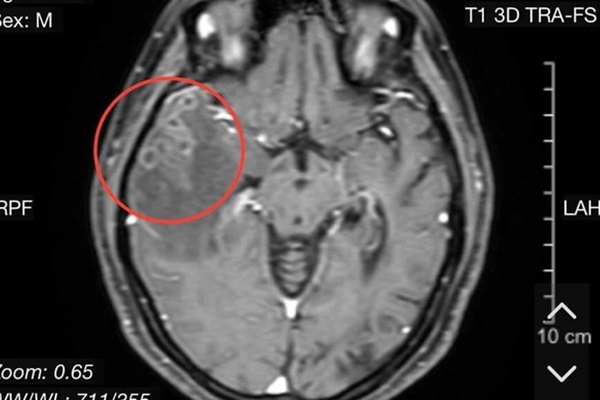

Chụp cổng hưởng từ sọ não cho thấy có nang sán trong não bệnh nhân. Ảnh: BVCC

Bệnh nhân được các bác sĩ cho các chỉ định làm cận lâm sàng. Qua hình ảnh chụp cộng hưởng từ sọ não có tiêm chất tương phản cho thấy người bệnh bị tổn thương não do sán. Kết quả xét nghiệm giải phẫu bệnh là mô não có nhiều ổ viêm hạt, trung tâm chất hoại tử, bao quanh lympho, đại bào nhiều nhân, tương bào và tế bào sợi. Kết luận tổn thương viêm não do nang sán.